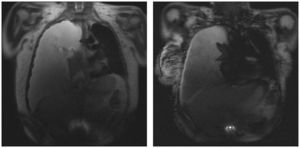

Se documentó derrame pleural derecho masivo (figs. 1–3), se realizó toracocentesis diagnóstica y terapéutica. Se obtuvo líquido pleural clasificado como exudado, con anticuerpos anti-DNA nativo positivos >250U/ml, y cultivos para bacterias, hongos y micobacterias negativos, con citología negativa para células malignas.

Se concluyó derrame pleural masivo secundario a actividad lúpica, y se trató con prednisona en dosis de 1mg/kg de peso y furosemida, con lo que se logró mejoría.